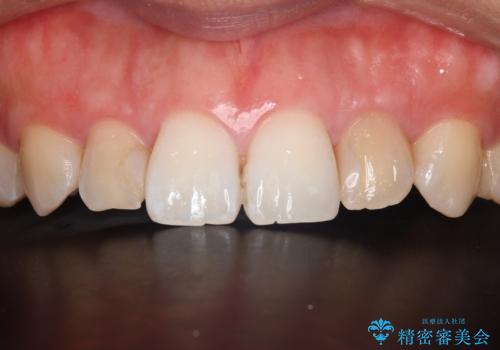

- 食べ物が歯間にはさまることを主訴に来院された患者様です。レントゲンより上顎両側切歯に根管治療が実施されていますが、被せ物が入っておらず、充填物に劣化像もみられました。歯の色の差も気にされていたのでオールセラミッククラウンにて治療いたしました。